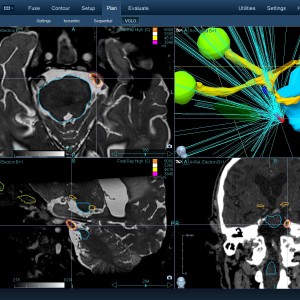

Στις παρακάτω φωτογραφίες θα δείτε παραδείγματα πλάνων θεραπείας καρκινικών όγκων με CyberKnife. Παρατηρήστε πόσο κοντά στους υγιείς ιστούς βρίσκονται οι καρκινικοί όγκοι που χρειάζεται να ακτινοβοληθούν. Μόνο με το CyberKnife και το προσωπικό πλάνο θεραπείας, μπορούν να ακτινοβοληθούν οι όγκοι χωρίς να πληγούν οι παρακείμενοι υγιείς ιστοί.

Μόνο με το CyberKnife και την κατάλληλη σχεδίαση της θεραπείας από έμπειρο νευροχειρουργό, μπορεί να ακτινοβοληθούν οι όγκοι χωρίς να επηρεαστούν από την ακτινοβολία οι υγιείς ιστοί. Αυτό εξασφαλίζει τη μέγιστη δυνατή απόδοση της ακτινοχειρουργικής θεραπείας των όγκων.

Με κόκκινο χρώμα περιγράφεται η περιοχή του όγκου.

Με μπλε, κίτρινο και πράσινο χρώμα περιγράφονται οι υγιείς ιστοί που δεν πρέπει να ακτινοβοληθούν.

Παρατηρήστε πόσο κοντά βρίσκεται ο όγκος με τους υγιείς ιστούς.

Παρατηρήστε τις πάρα πολλές δέσμες του CynerKnife που ακτινοβολούν τους όγκους από διαφορετικές γωνίες ώστε να μην προσβληθούν από την ακτινοβολία οι υγιείς ιστούς.